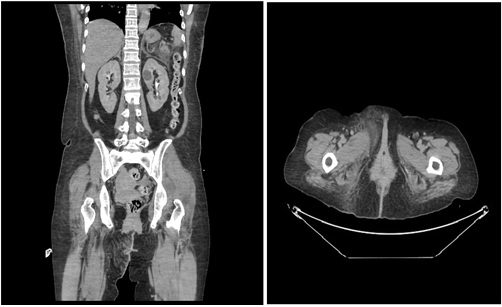

After stabilization, the patient underwent IV contrast CT scan of the abdomen and pelvis, which revealed diffuse interstitial pancreatitis with peri-pancreatic inflammation and minor fluid collection (figure 1). In addition, diffuse inflammatory changes were noted in the skin and subcutaneous tissues of the pubic region and labia extending into the perineum, mainly on the right side.

Figure 1: A) left B) right diffuse inflammatory changes in the skin and subcutaneous tissues of the pubic region and labia extending into the perineum.